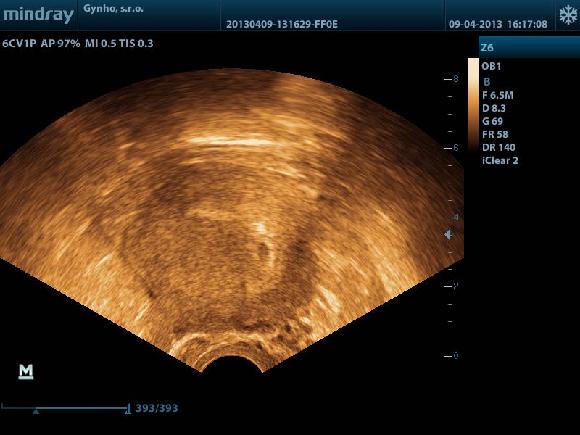

tohle je 5+4,,18 denpo ET